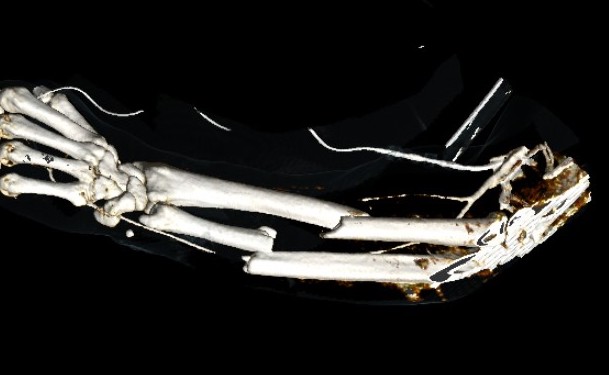

Radial fracture malunion requiring corrective osteotomy